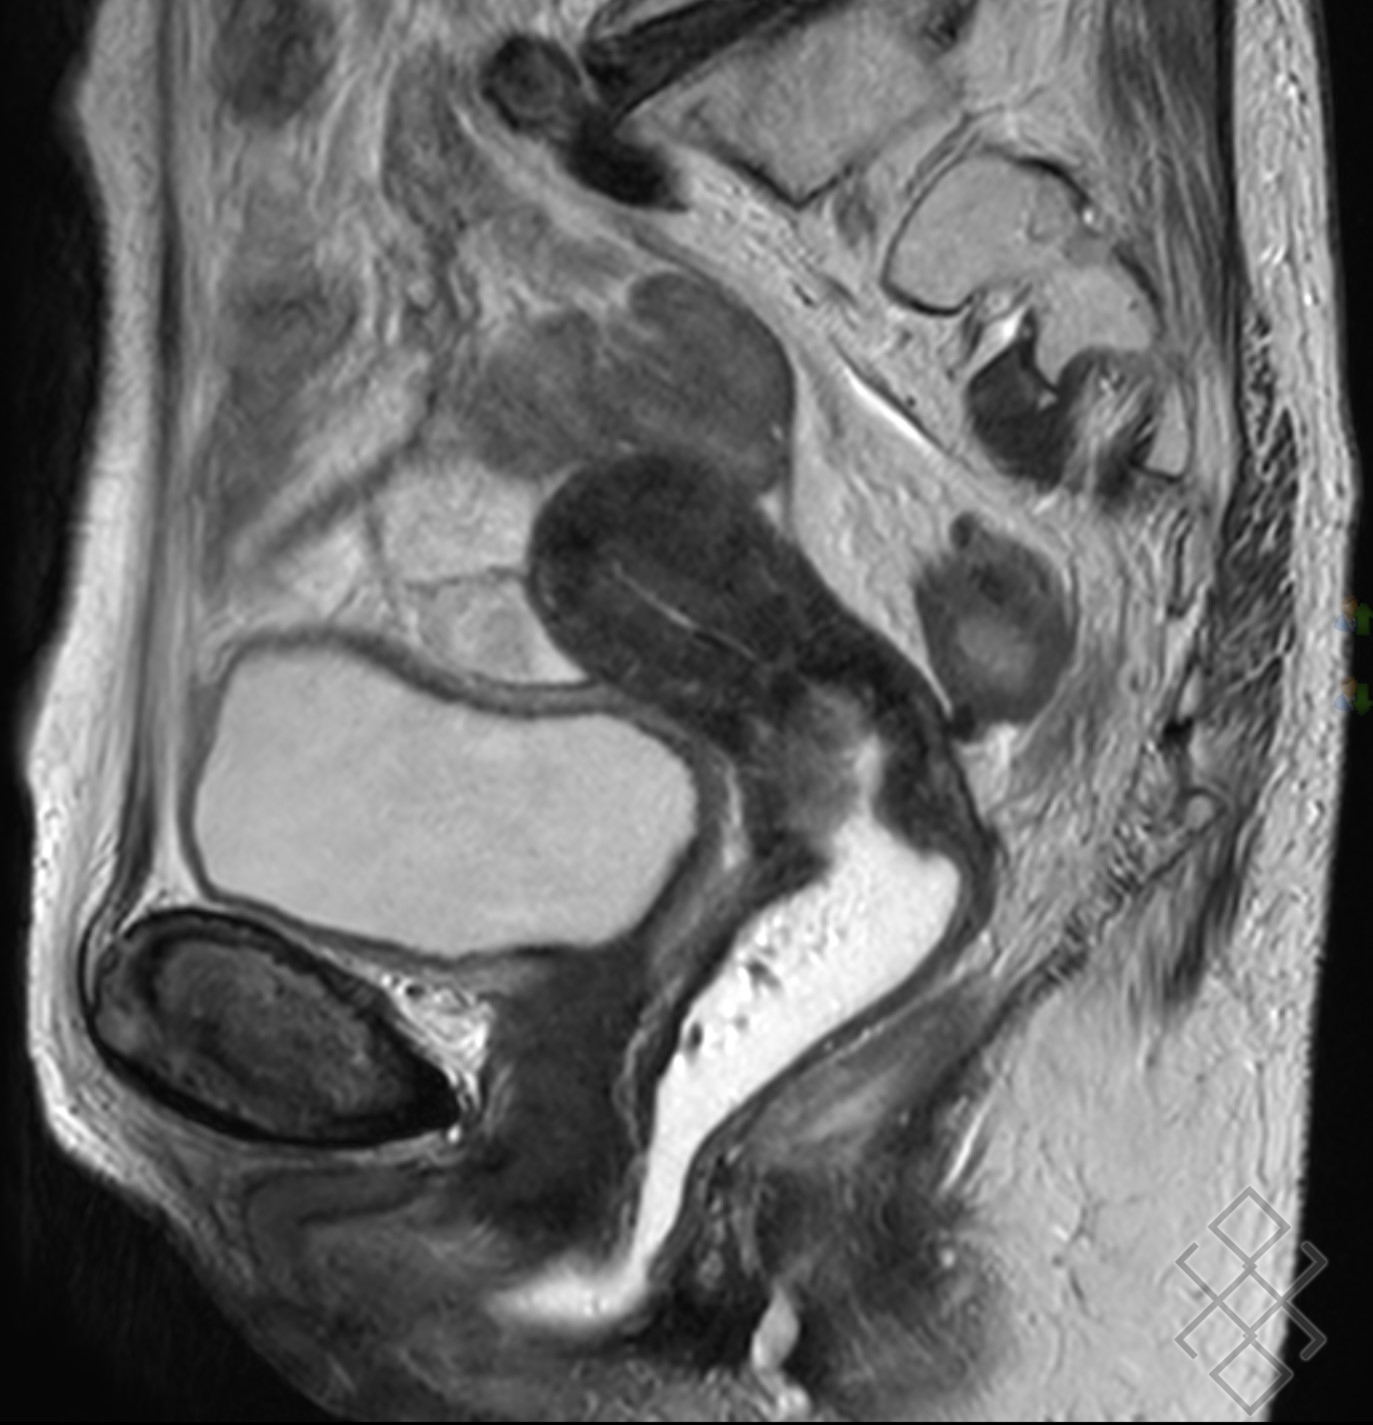

Une préparation digestive par lavement rectal (Microlax) est recommandée afin d'améliorer la qualité des images. du Microlax et éventuellement du produit de contraste gadoliné en fonction de l'indication de l'IRM pelvienne.

IRM pelvienne Centre de radiologie Olympe Imagerie Antony. Comment se préparer à une IRM pelvienne ? "En fonction de la demande faite par le médecin généraliste ou spécialiste, le radiologue décidera s'il est nécessaire d'effectuer un lavement évacuateur quelques heures avant l'examen, s'il faut être à jeun (généralement six heures avant l'examen) ou s'il faut avoir une vessie pleine ou vide", répond la spécialiste. AVANT L'EXAMEN Apporter les produits prescrits lors de la prise de rendez-vous